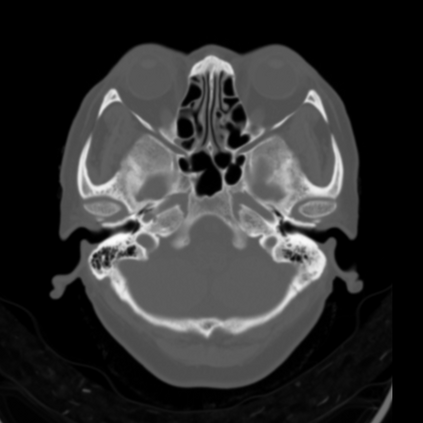

CT reconstruction provides radiologists with images for diagnosis and treatment, yet current deep learning methods are typically limited to specific anatomies and datasets, hindering generalization ability to unseen anatomies and lesions. To address this, we introduce the Multi-Organ medical image REconstruction (MORE) dataset, comprising CT scans across 9 diverse anatomies with 15 lesion types. This dataset serves two key purposes: (1) enabling robust training of deep learning models on extensive, heterogeneous data, and (2) facilitating rigorous evaluation of model generalization for CT reconstruction. We further establish a strong baseline solution that outperforms prior approaches under these challenging conditions. Our results demonstrate that: (1) a comprehensive dataset helps improve the generalization capability of models, and (2) optimization-based methods offer enhanced robustness for unseen anatomies. The MORE dataset is freely accessible under CC-BY-NC 4.0 at our project page https://more-med.github.io/